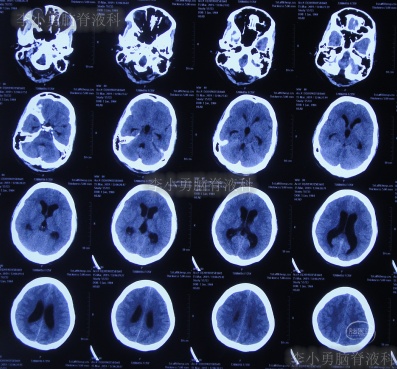

图-4:2019年2月24日头颅CT

但腰椎穿刺术后头痛仅短暂缓解1天左右,在该院继续治疗8天,仍间断头痛发热,间断给予腰穿治疗,化验脑脊液白细胞高,曾先后3次查头颅CT(图-5、图-6、图-7)均示脑室并未明显扩张。

图-5:2019年2月26日头颅CT

图-6:2019年2月27日头颅CT

图-7:2019年3月5日头颅CT

图-10:2019年3月15日头颅CT